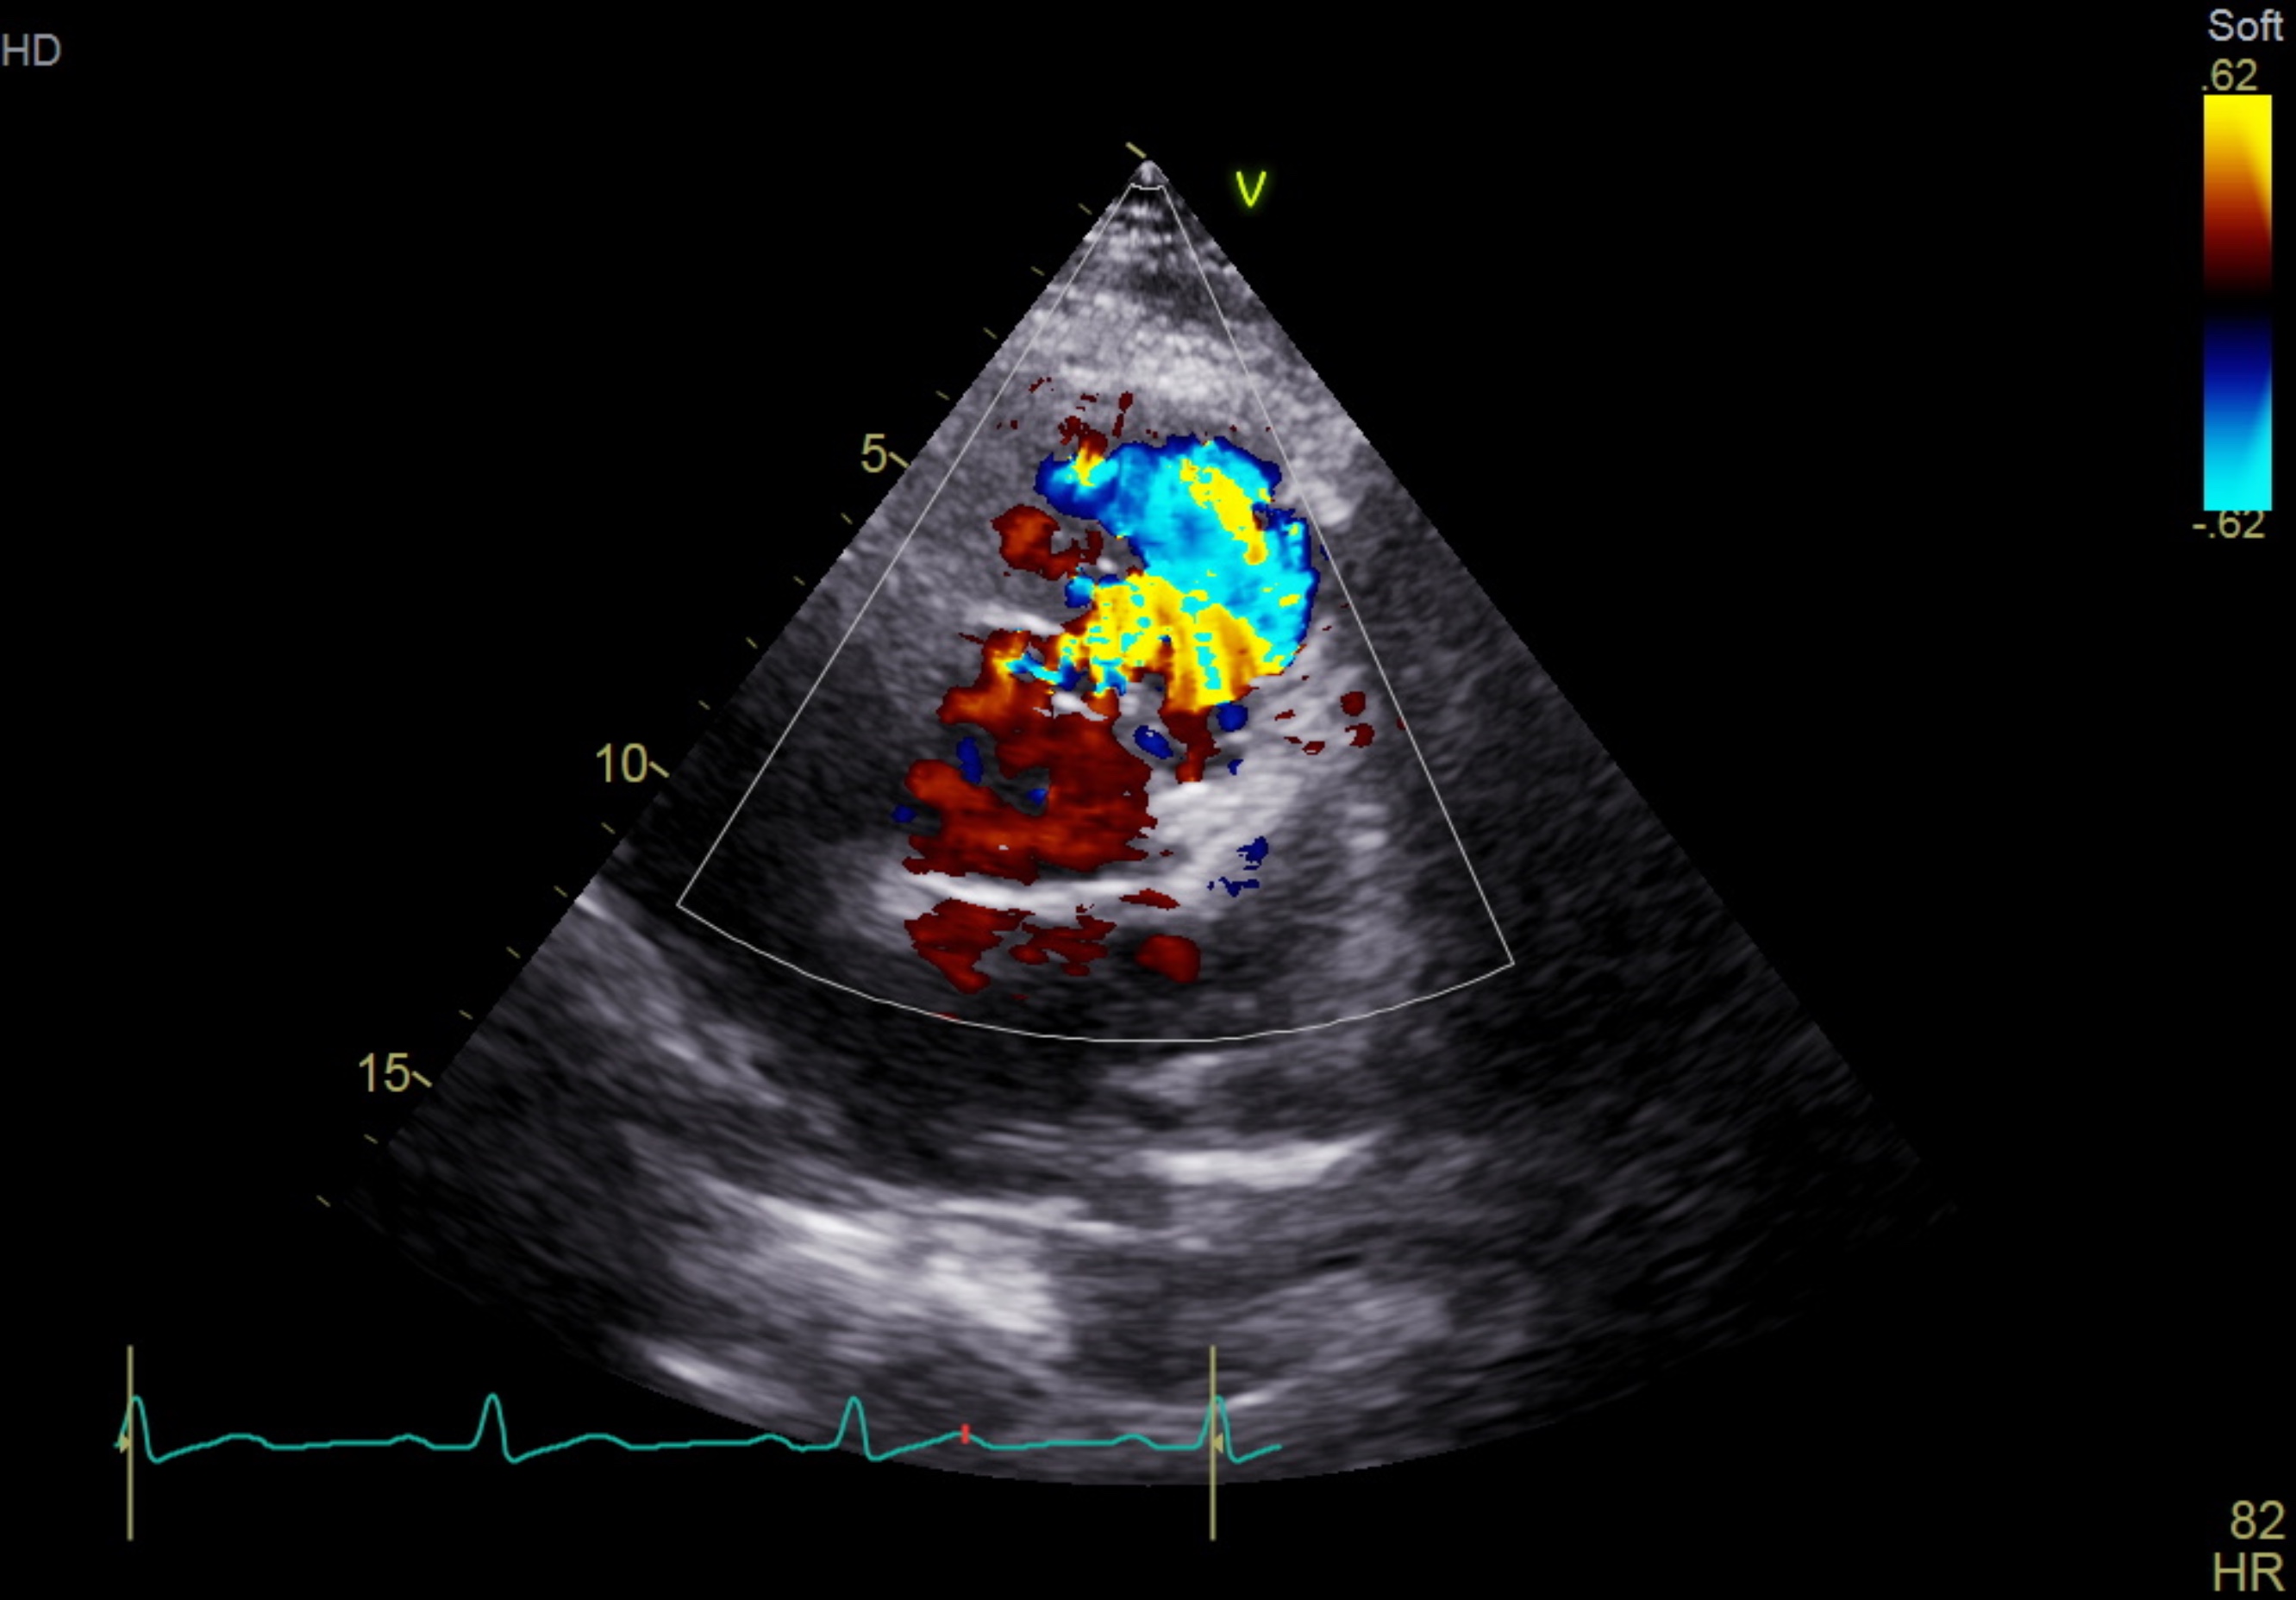

The electrocardiogram shows sinus rhythm, normal axis with left ventricular hypertrophy. The chest X-ray shows a normal cardiac silhouette without prominent pulmonary trunk. His NT-ProBNP was raised with normal troponin reading.The trans-thoracic echocardiogram revealed a ruptured right sinus of valsalva (SOV) with left to right shunting to right ventricle. The aorta is dilated without aortic valve regurgitation. The left ventricle is dilated with 63% of ejection fraction.

PSAX CFM.mp4